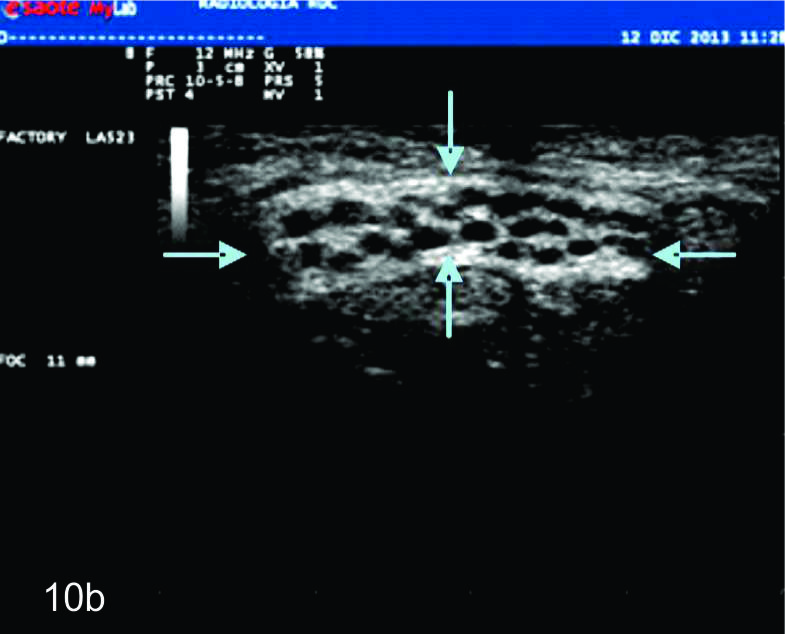

Figura 10

Hamartoma fibrolipomatoso del nervio mediano

A y B, cortes transversales en antebrazo y puño, las flechas azules señalan al nervio mediano aumentado de tamaño con fascículos engrosados. C- Corte longitudinal con hallazgos similares en plano longitudinal del nervio (flechas azules).

Dada las características ultrasonográficas normales de los nervios, algunas variantes anatómicas pueden ser reconocidas por este método. Entre ellas la bifurcación proximal del mediano en el puño es una de las más frecuentes. De manera similar algunas anomalías heredables y del desarrollo del sistema nervioso periférico, como el agrandamiento fusiforme del nervio mediano por tejido fibroadiposo (denominado hamartoma fibrolipomatoso (Fig.10), la hipertrofia de los nervios en el síndrome de Charcot-Marie-Tooth y el aumento de los nervios en la neuropatía hereditaria secundaria a parálisis por compresiones pueden ser reconocidas por ultrasonido. En estas enfermedades, los hallazgos ultrasonográficos pueden contribuir a la comprensión de la fisiopatología demostrando de forma no invasiva algunos hallazgos morfológicos de interés (1).